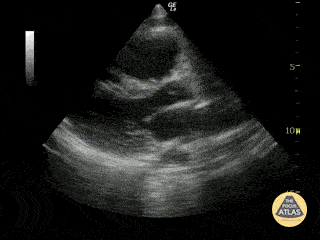

Left Ventricular Dysfunction - Cardiac Arrest with Agonal Rhythm